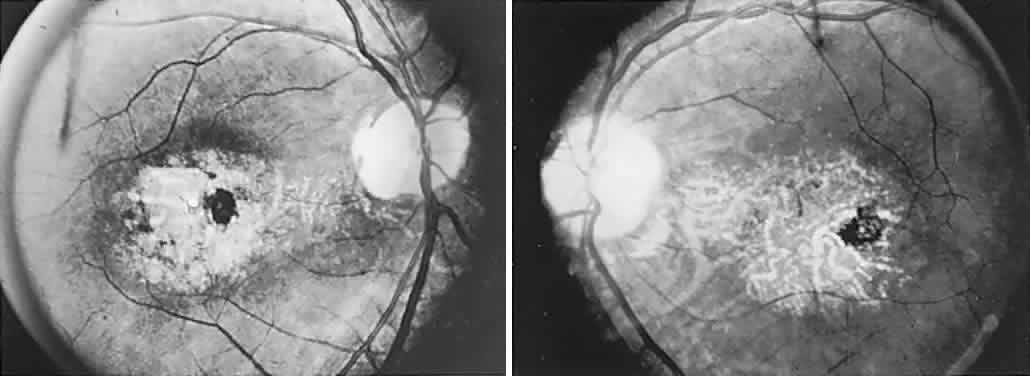

The ganglion cell layer of the retina is a principal site of abnormal accumulation of anomalous storage products, such that ophthalmoscopic changes are observable either in the form of retinal “graying” or the well-known cherry-red spot. The ganglion cell layer densely surrounds the thin fovea, which transmits the normal red color of underlying choroid (Fig. 4). The storage disorders with cherry-red spot or macular graying are listed in Table 2.27

Fig. 4. “Cherry-red spot” of advanced Tay-Sachs disease (gangliosidosis). Note the central foveal window surrounded by a ring of densely opaque retinal ganglion cell layer; also, optic atrophy.